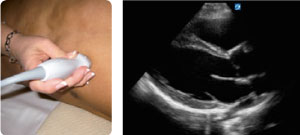

VISTA DEL EJE LARGO PARAESTERNAL

Identifique VD, VI y LA. Dirija el transductor de forma perpendicular hacia el lado izquierdo del pecho del paciente en el espacio paraesternal 4-6. Mantenga la orientación del transductor hacia el hombro derecho del paciente y el marcador de orientación entre las 9 y las 11. Es la mejor vista para observar la función, el tamaño y los derrames del VI.